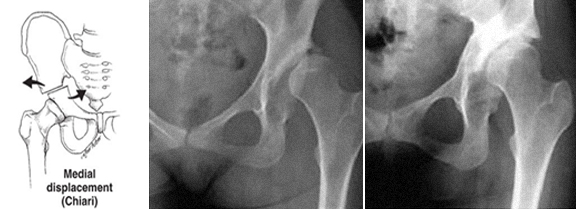

· Shelf (butée), na actualidade raramente utilizada, resultados díspares nas séries publicadas.

Em algumas ancas displásicas há uma cabeça aplanada e com um volumoso osteófito medial (capital drop) e a osteotomia de valgização pode aumentar a congruência articular, a medialização do centro de rotação, aumentar o comprimento do membro, melhorar a função dos abdutores pelo melhor posicionamento do grande trocanter.